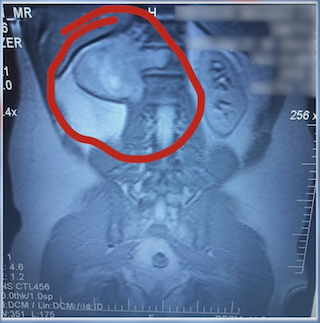

- Magnetic resonance imaging (MRI) scan uses radio waves and a powerful magnet to produce detailed images of bones to check for problems.